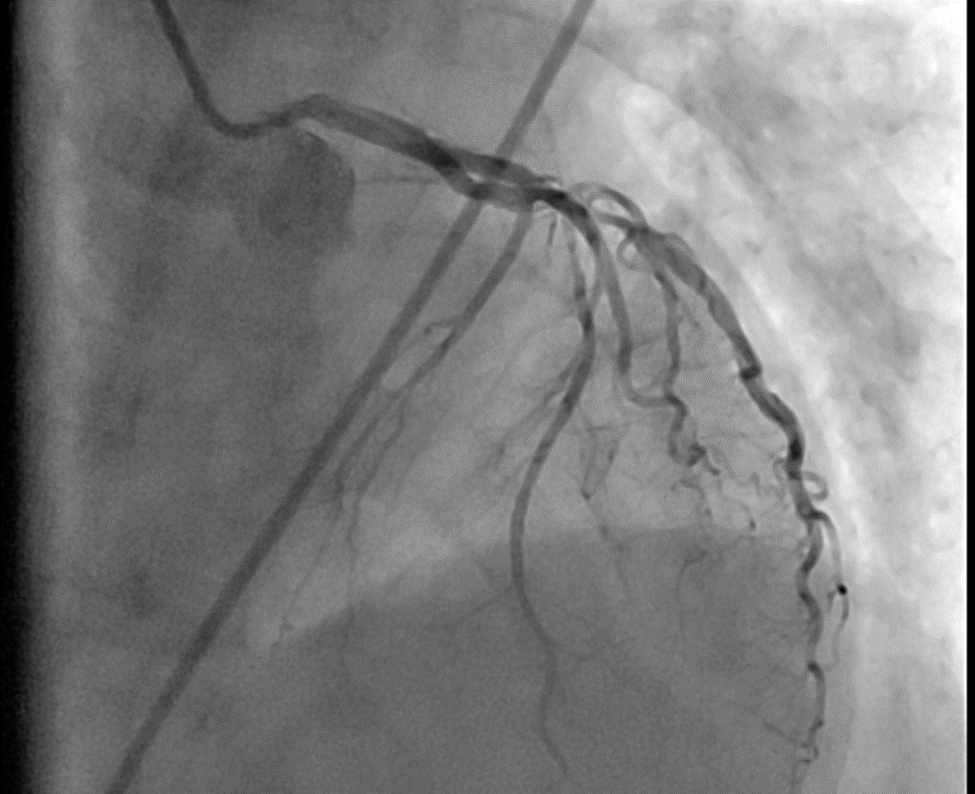

Case Summary: This case report presents the case of a 70-year-old female who presented to a community hospital in Pakistan in January 2024 with chest pain and progressive dyspnea that started seven days after an MI diagnosis. Her echocardiogram revealed an apical VSD, while coronary angiography confirmed dual-vessel coronary artery disease. Subsequently, she underwent elective subacute surgical repair of a 3x3 cm apical VSD along with coronary artery bypass grafting (CABG) and intra-aortic balloon pump placement. Postoperatively, she developed a ventricular thrombus, which was managed with anticoagulation. Follow-up echocardiography demonstrated marked clinical improvement.